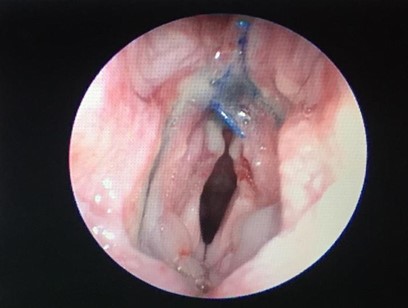

Спустя 2,5 месяца после установки имплантата наблюдается прорастание ткани сквозь перфорации (рис. 1 в) и его полная интеграция в гортани пациента.

Рисунок 1. Результаты клинических испытаний: а) модель имплантата; б) имплантат в гортани мопса непосредственно после установки; в) интеграция имплантата через 9 дней после операции; г) рентгеновский снимок пациента, стрелка указывает на имплантата